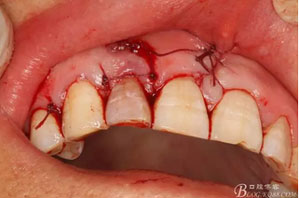

圖20.間斷縫合。

圖21.術(shù)后的x根尖片影像情況。12根尖區(qū)MTA充填完好。